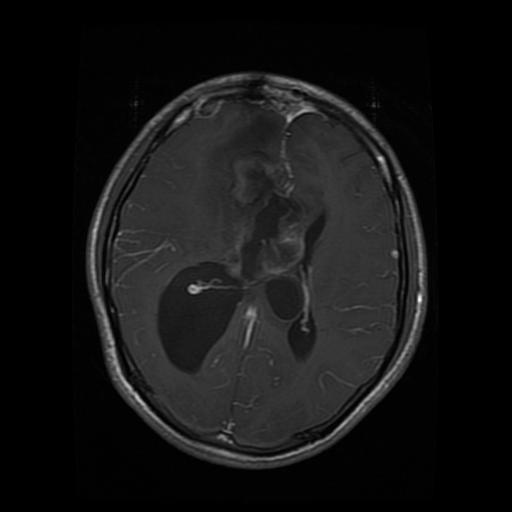

Figure 2: Samples of Meningioma segmentation across different imaging planes

Meningioma: Meningiomas arise from the meninges and are generally well‑circumscribed and homogeneous, making them easier to segment. However, their location adjacent to critical structures such as dural sinuses and cranial nerves can complicate diagnostic tasks. An example of a meningioma and its segmentation mask is presented in Figure 2, illustrating the clarity of its boundaries.